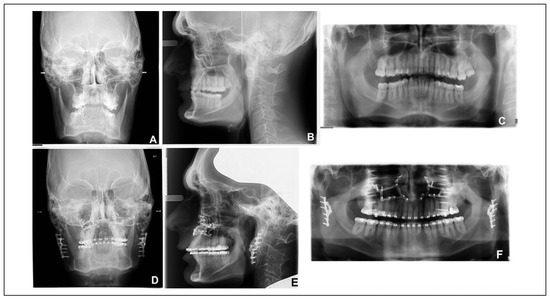

CAD/CAM Engineered Patient-Specific Impants as a Reposition Device in Le Fort I and Modified Subcondylar Osteotomies: Case Report of Facial Deformity Correction in Acromegaly

by Juho Suojanen, Zlatan Hodzic, Tuula Palotie and Patricia Stoor

Craniomaxillofac. Trauma Reconstr. 2020, 13(3), 226-236; https://doi.org/10.1177/1943387520924521 - 6 Jul 2020

Acromegaly is a medical condition where elevated growth hormone or insulin-like growth factor I levels cause several changes in the craniofacial soft and hard features. We report the correction of facial deformity and posterior open bite with Le Fort I and modified subcondylar [...] Read more.

Acromegaly is a medical condition where elevated growth hormone or insulin-like growth factor I levels cause several changes in the craniofacial soft and hard features. We report the correction of facial deformity and posterior open bite with Le Fort I and modified subcondylar osteotomies in a patient affected by acromegaly. Computer-aided design and manufacturing generated saw and drill guides were used to perform osteotomies and segment removal. The placement of the patient-specific implants (PSIs) was guided by predesigned drill holes ensuring the required and planned movement of the jaws and position of the PSIs. After segment removal, the PSIs fitted the predesigned drill holes with high precision and were secured without problems. The planned amount of mandibular and maxillary movement was achieved. The occlusion and osteotomies remained stable for the follow-up of 22 months. The use of PSIs combined with guided surgery can be beneficial for selected cases with asymmetry or posterior open bite enabling new approaches and yielding good functional and aesthetic outcome. The modification of conventional ramus osteotomy combined with utilization of ramus segment removal and the use of PSI for reposition is an interesting and promising technique for rare conditions with ramus height asymmetry. Full article